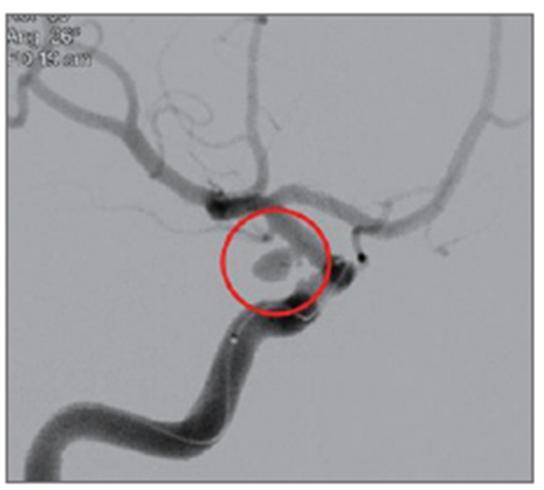

▶뇌동맥류 & 뇌 지주막하 출혈 사진

5_뇌동맥류, 뇌지주막하출혈 사진1.jpg

5_뇌동맥류, 뇌지주막하출혈 사진2.jpg

1. 뇌혈관조영술에서 혈관벽이 풍선처럼 부풀어 오른 뇌동맥류 모습(빨간 원안).

2. 뇌지주막하출혈 뇌CT. 뇌 가운데에 흰색으로 보이는 별모양의 급성 출혈이 보임.